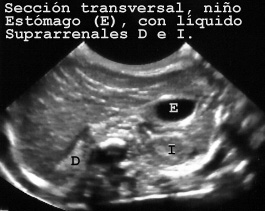

En adultos podemos llenar el estomago con agua ayudados de una aguja y jeringuilla a través del epigastrio. En los niños usamos una sonda nasogastrica y también se suele llenar el intestino. En la Fig 46 el estomago de un niño y el intestino presentan líquido en su interior. En esta imagen son visibles las suprarrenales. En el centro se observa la columna vertebral cortada de través y la médula espinal en el centro.